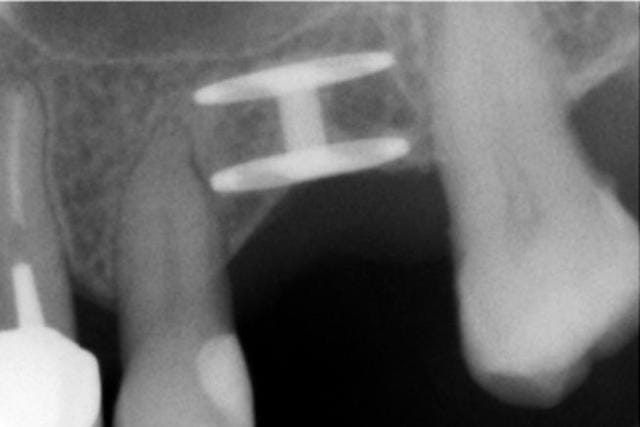

ah bon je ne suis pas d'accord voila un de mes cas...

Victory 1 sqoj91 - Eugenol

Victory 2 wwphs8 - Eugenol